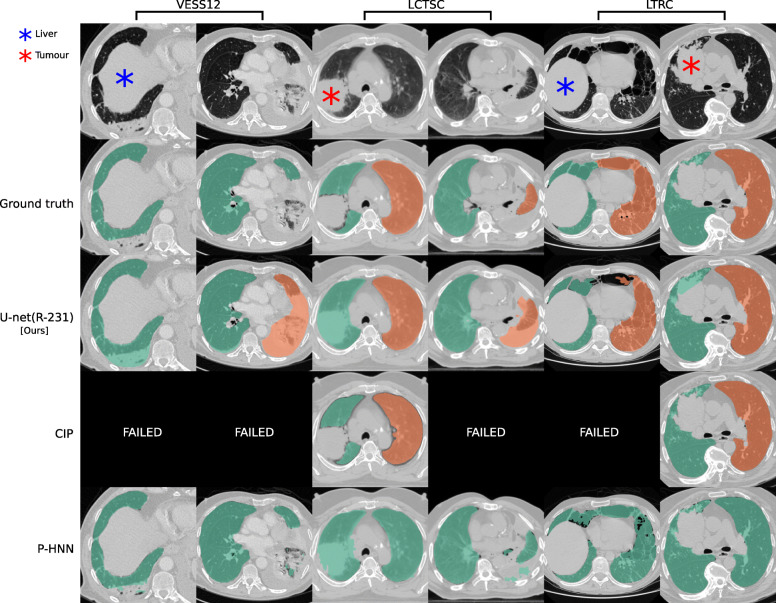

Fig. 3.

Ground truth annotations in public datasets lack coverage of pathologic areas. Segmentation results for cases in public datasets where the masks generated by our U-net(R-231) yielded low Dice similarity coefficients when compared to the ground truth. Note that public datasets often do not include high-density areas in the segmentations. Tumours in the lung area should be included in the segmentation while the liver should not

Compared to readily available trained P-HNN model, the U-net trained on the R-231 routine dataset [U-net(R-231)] yielded mean DSC, HD95, and MSD scores of 0.98 ± 0.03, 3.14 ± 7.4, 0.62 ± 0.93 versus 0.94 ± 0.12, 16.8 ± 36.57, 2.59 ± 5.96 (p = 0.024, 0.004, 0.011) on the merged test dataset (All, n = 62). For comparison with the CIP algorithm, only volumes for which the algorithm did not fail were considered. On the merged dataset (All, N = 62), the algorithms yielded mean DSC, HD95, and MSD scores of 0.98 ± 0.01, 1.44 ± 1.09, and 0.35 ± 0.19 for the U-net(R213) compared to 0.96 ± 0.05, 4.65 ± 6.45, and 0.91 ± 1.09 for CIP (p = 0.001, < 0.001, < 0.001). Detailed results are given in Table 4. Figure 2 shows qualitative results for cases from the routine test sets, and Fig. 3 shows cases for which the masks generated by the U-net(R-231) model yielded low DSCs when compared to the ground truth.

There are limitations of our study that should be taken into account. Routine clinical data vary between sites. Thus, extraction of a diverse training dataset from clinical routine may only be an option for centres that are exposed to a wide range of patient variety. Evaluation results based on public datasets are not fully comparable. For example, the models trained on routine data compared to other datasets yielded lower performance in terms of DSC on the LCTSC test data. However, the lower scores for models trained on routine data in LCTSC can be attributed to the lack of very-dense pathologies in the ground truth masks. Figure 3 illustrates cases for which the R-231 model yielded low DSC. The inclusion or exclusion of pathologies such as effusions into lung segmentations is a matter of definition and application. While pleural effusions (and pneumothorax) are technically outside the lung, they are assessed as part of lung assessment and have a substantial impact on lung parenchyma appearance through compression artefacts. Neglecting such abnormalities would hamper automated lung assessment, as they are closely linked to lung function. In addition, lung masks that include pleural effusions greatly alleviate the task of effusion detection and quantification, thus making it possible to remove effusions from the lung segmentation as a post-processing step.